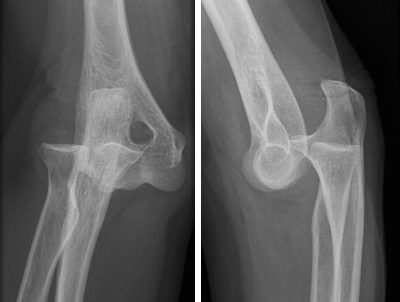

Pergunta: Na fratura fechada e desalinhada de osso longo, qual é a conduta correta? a) Colocar gelo no local e não imobilizar, uma vez que a fratura está desalinhada.

b) Realinhar a fratura bem lentamente e imobilizar o local atingindo a articulação acima e abaixo da lesão. c) Colocar gelo sobre a área em desalinho e fazer curativo compressivo antes de imobilizar apenas o local da fratura. d) Imobilizar o local, atingindo a articulação acima e abaixo da lesão, sem realinhar a fratura. Resposta: d) Imobilizar o local, atingindo a articulação acima e abaixo da lesão, sem realinhar a fratura. -

Pergunta: Ao socorrer uma vítima com fratura no braço, é importante imobilizar o membro até que chegue o socorro especializado ou a vítima seja transportada para o hospital. Sobre a forma correta de realizar essa imobilização, analise as afirmativas a seguir: I. A tala utilizada para realizar a imobilização deve ultrapassar as articulações acima e abaixo da fratura.

II. Em caso de fratura exposta, deve-se tentar recolocar o osso no lugar correto antes de realizar a imobilização. III. Para improvisar uma tala pode-se usar qualquer material rígido ou semirrígido como madeira ou papelão. Assinale a alternativa CORRETA: a) As sentenças I e III estão corretas. b) As sentenças I e II estão corretas. c) Apenas a sentença I está correta. d) Apenas a sentença III está correta. Resposta: a) As sentenças I e III estão corretas.